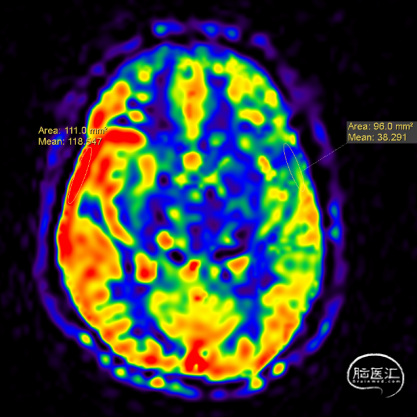

术后即刻CT

术后24小时复查颅脑MR未见明显出血。

颅脑灌注成像提示高灌。